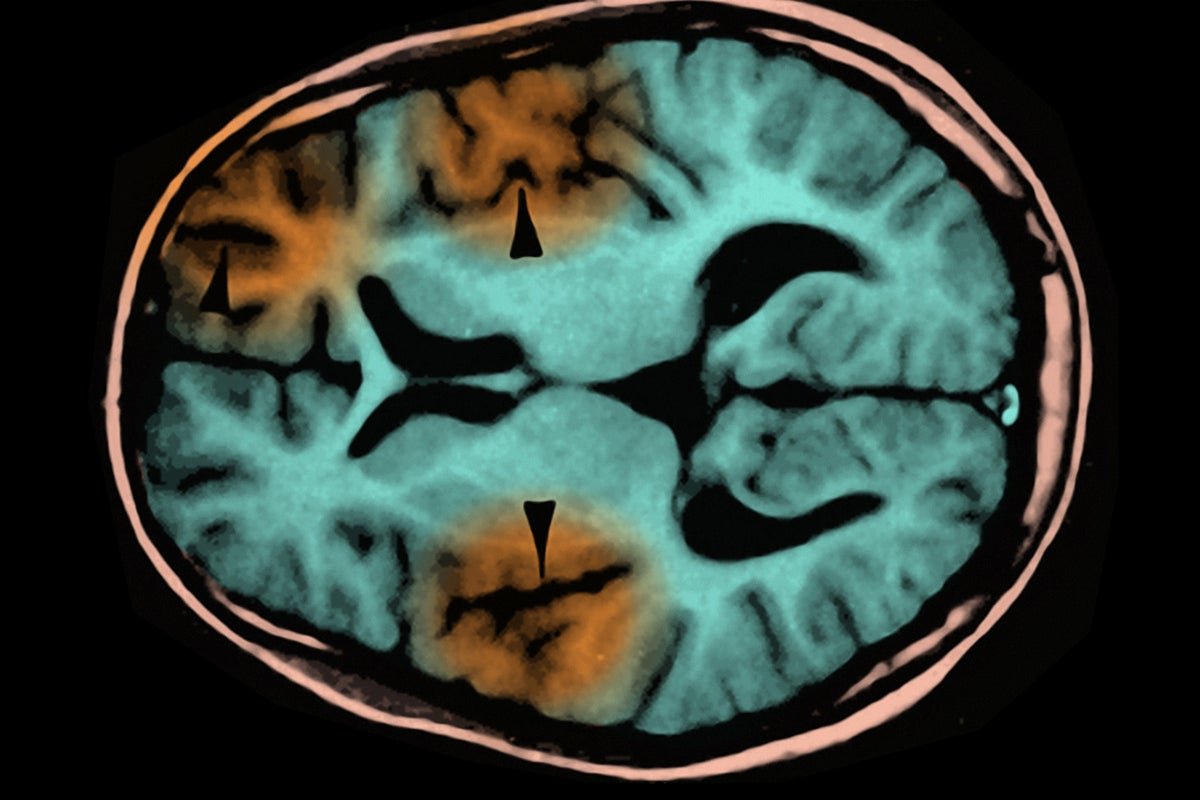

An MRI scan showing subacute sclerosing panencephalitis, a complication of measles infection.

The child who died suffered from subacute sclerosing panencephalitis (SSPE), a progressive brain disorder that usually develops two to 10 years after a measles infection. The measles virus appears to mutate into a form that avoids detection by the immune system, allowing it to hide in the brain and eventually destroy neurons.

“It’s just a virus that goes unchecked and destroys brain tissue, and we have no therapy for it,” said Walter Orenstein, an epidemiologist and professor emeritus at Emory University, to Scientific American earlier this year.

SSPE is one of several side effects of measles that go beyond the coughing, runny nose and characteristic rash of the original infection. Measles can also cause encephalitis, a faster-occurring brain inflammation, in one in every 1,000 people who are infected because the virus causes the immune system to attack a protein produced by certain brain cells. This inflammation kills about one in five people who develop it.